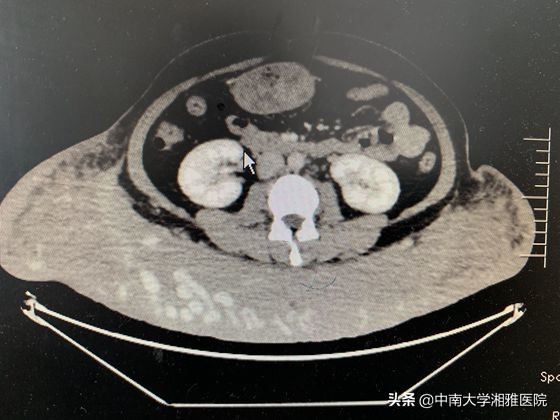

术前血管造影(CTA)横断面图。

烧伤重建外科主任张丕红教授接诊后,发现患者身体多处有咖啡色色素沉着,臀部皮下肿块已大于篮球,约50*75cm2,肿块表面的皮肤温度升高明显、逾38度。血管造影等一系列检查显示,肿块内血管组织相当丰富,大血管窦多,且纤维瘤与周围肌肉连结紧密,几乎没有间隙。张丕红教授表示,如果不做手术,不仅肿瘤巨大、影响外观,且一旦出现皮肤破损,极易引发大出血,导致休克、甚至危及生命,因此,手术势在必行。